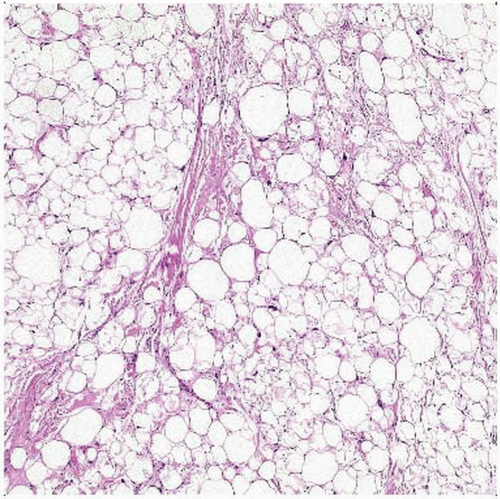

Spindle cell lipoma is composed of a proliferation of adipocytes and …

Lipoma – spindle cell – histology | Image | Radiopaedia.org